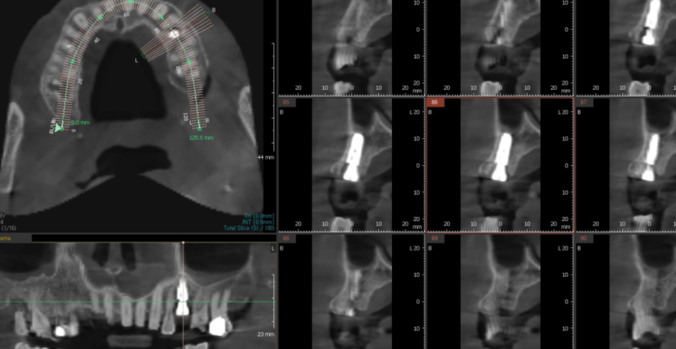

임플란트 진단을 위해 ct를 찍어보았는데

다른 치아도 뼈가 많이 녹은 것이 발견

환자분께 안 좋은 상황임을 안내해드렸습니다.

231211

진단도 ct로 놓치는 부분 없이

수술도 ct로 정확하게 진행합니다.